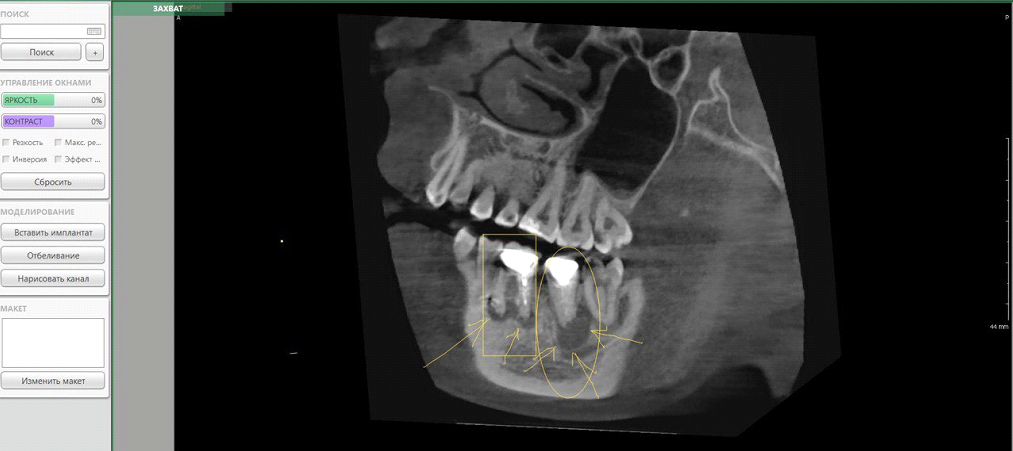

Вот здесь врач рассматривает каждый зуб по этому алгоритму. Эти два зуба он диагностирует на десятках визуализаций в разных проекциях, но я сделал скриншот так, чтобы вам было понятно:

Под стрелками тёмные пятна в области верхушек корней — это признаки воспалительного процесса. Зуб в прямоугольнике решено было удалить из-за несостоятельности коронковой части (это мы оценили, ещё непосредственно посмотрев в пациента в микроскоп). Второй оставили — он ещё поживёт.